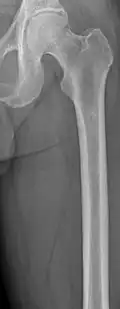

Femur with multiple myeloma lesions -

Same femur before myeloma lesions for comparison -